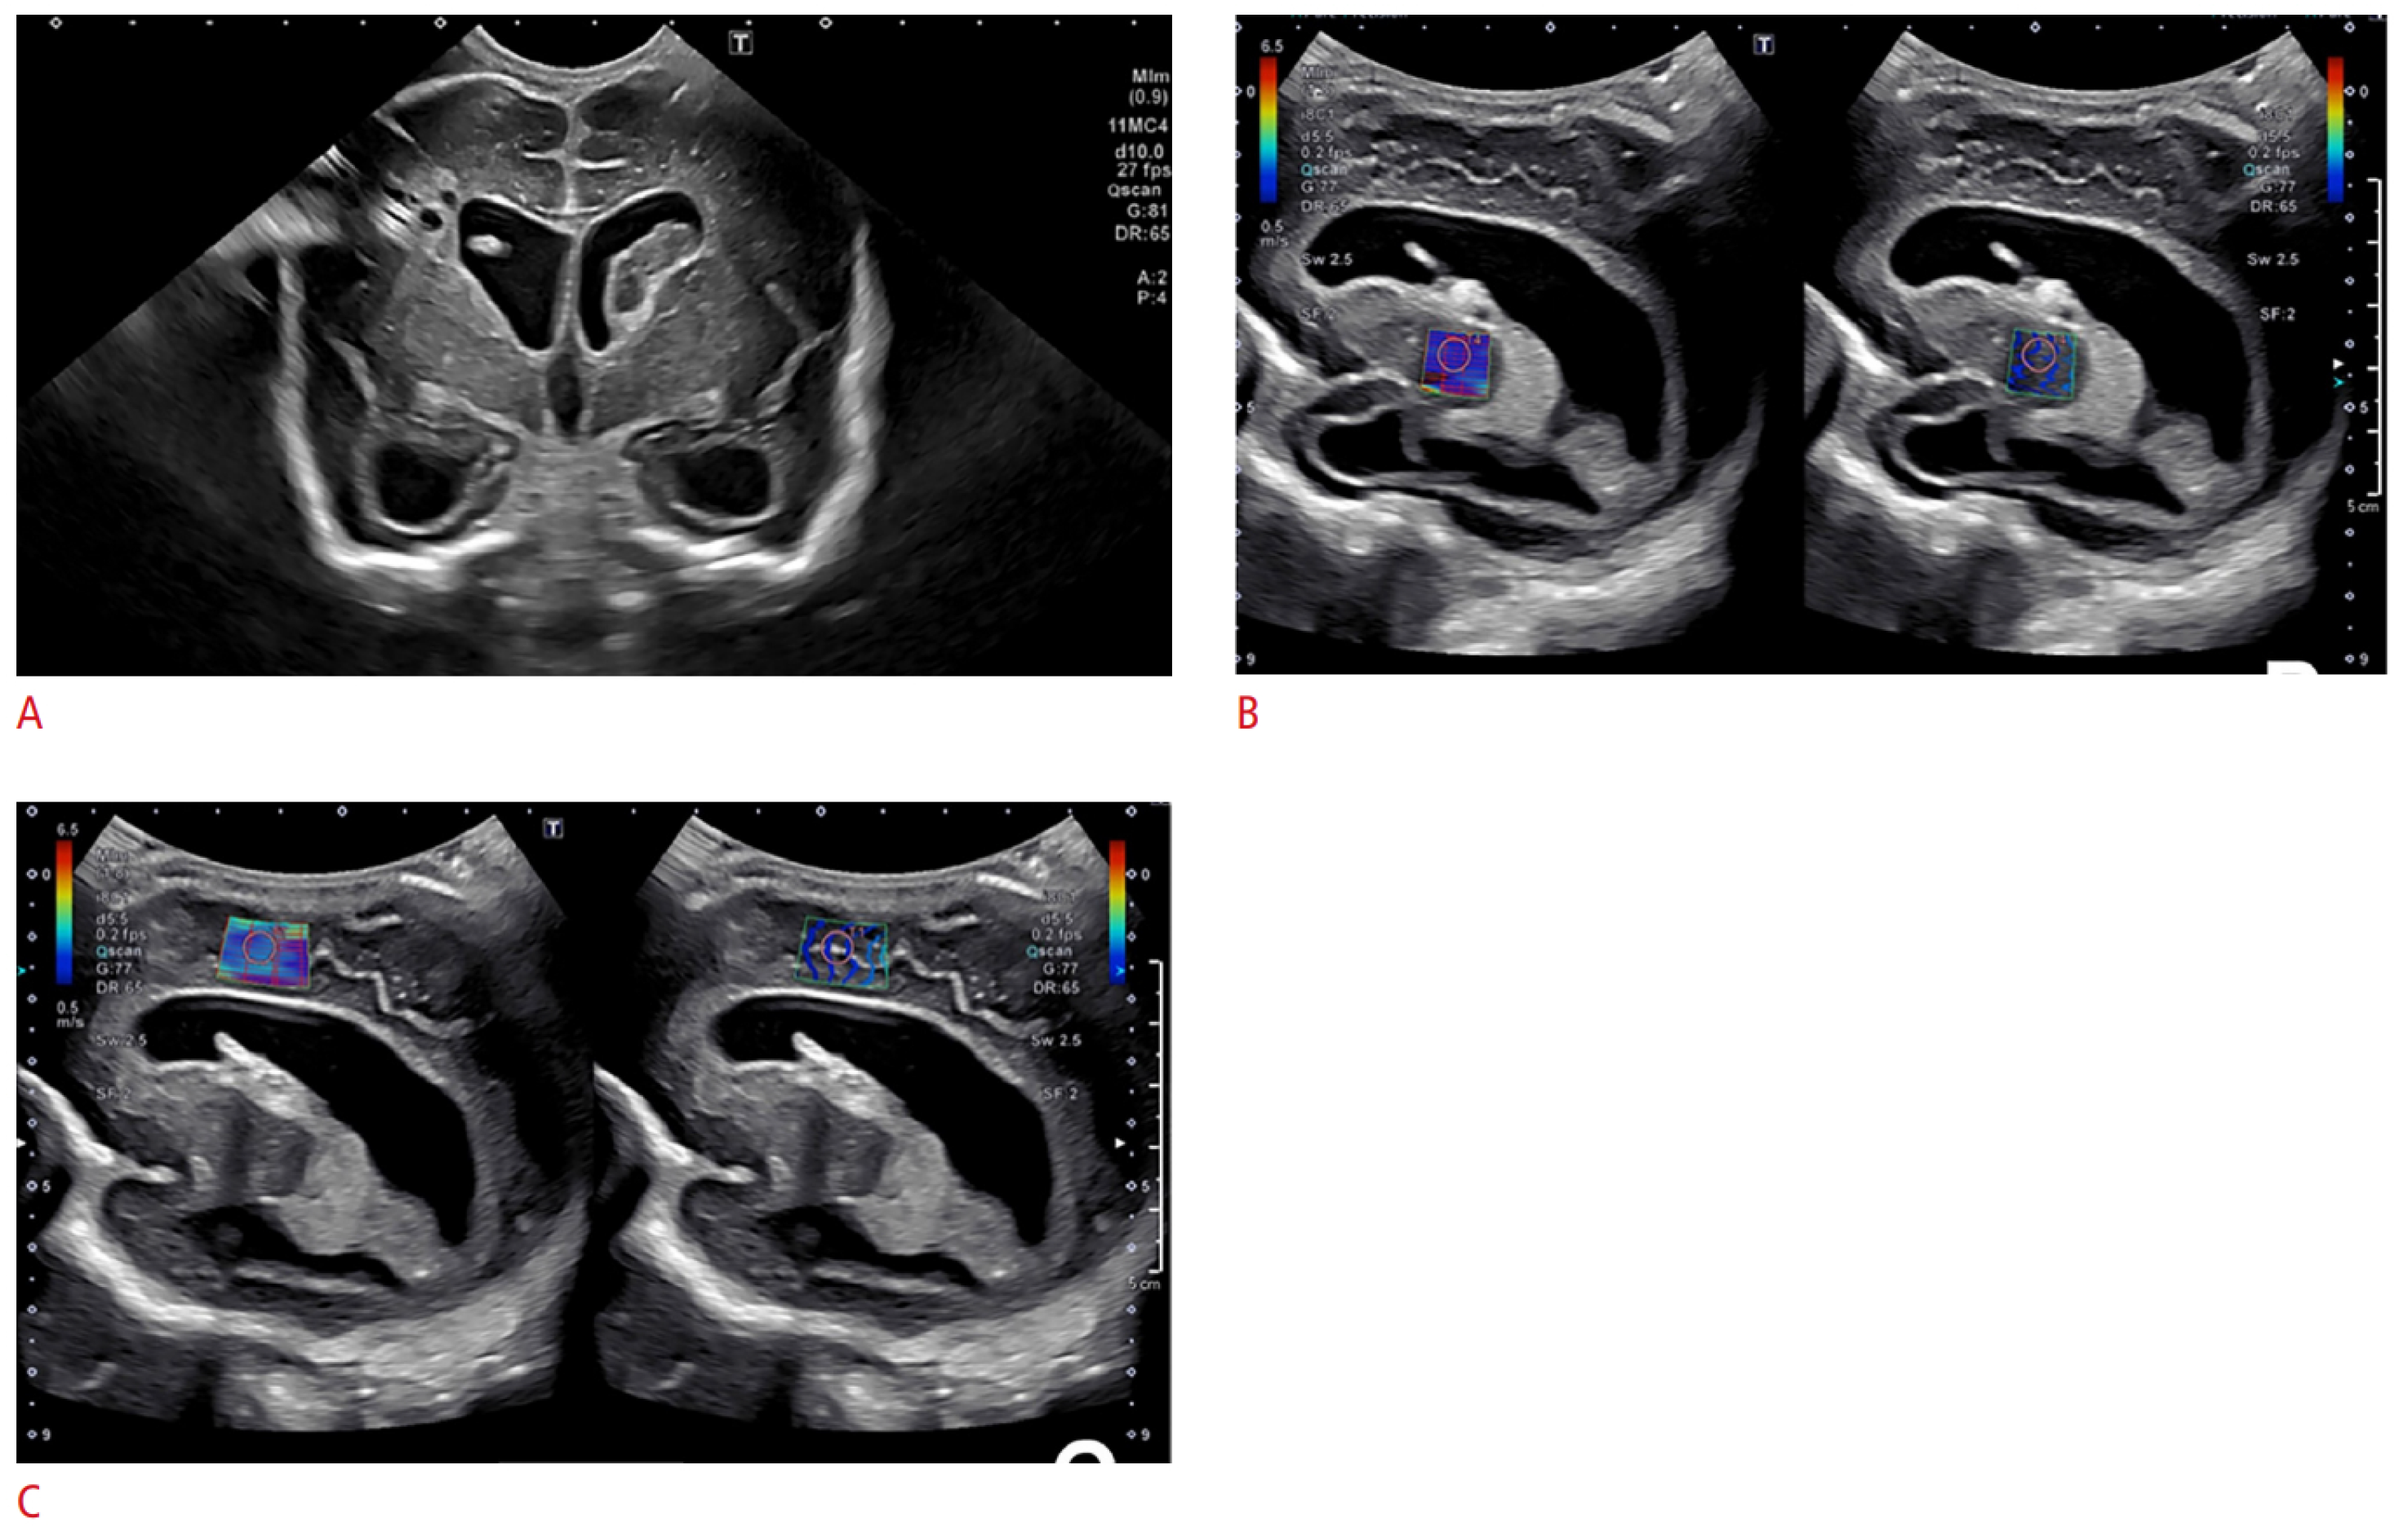

- Bailey, C.; Huisman, T.A.G.M.; de Jong, R.M.; Hwang, M. Contrast-Enhanced Ultrasound and Elastography Imaging of the Neonatal Brain: A Review. J. Neuroimaging 2017, 27, 437–441. [Google Scholar] [CrossRef]

- El-Ali, A.M.; Subramanian, S.; Krofchik, L.M.; Kephart, M.C.; Squires, J.H. Feasibility and reproducibility of shear wave elastography in pediatric cranial ultrasound. Pediatr. Radiol. 2020, 50, 990–996. [Google Scholar] [CrossRef]

- deCampo, D.; Hwang, M. Characterizing the neonatal brain with ultrasound elastography. Pediatr. Neurol. 2018, 86, 19–26. [Google Scholar] [CrossRef] [PubMed]

- Hwang, M.; Zhang, Z.; Katz, J.; Freeman, C.; Kilbaugh, T. Brain contrast-enhanced ultrasonography and elastography in infants. Ultrasonography 2022, 41, 633–649. [Google Scholar] [CrossRef]